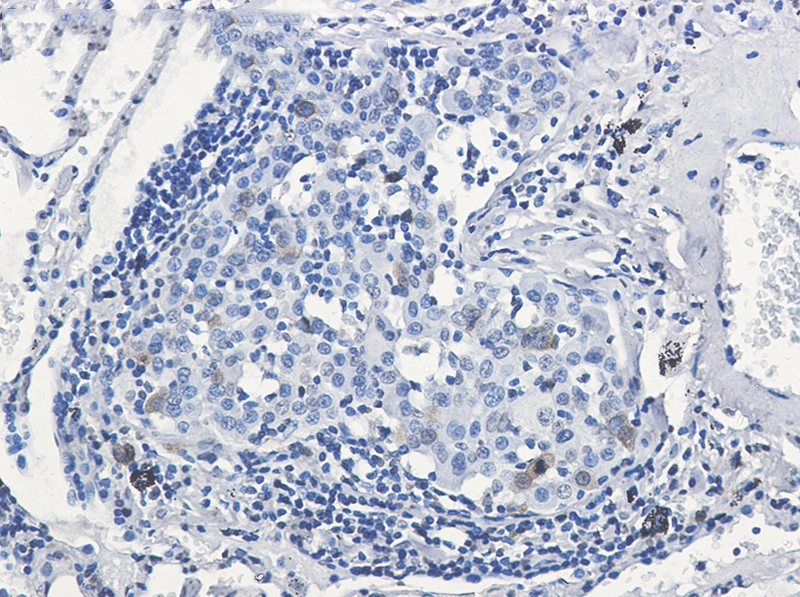

Immunohistochemistry of Cdk1/2 (phospho-Thr14) in paraffin-embedded Human lung cancer tissue using Cdk1/2 (phospho-Thr14) Rabbit mAb at dilution 1/50